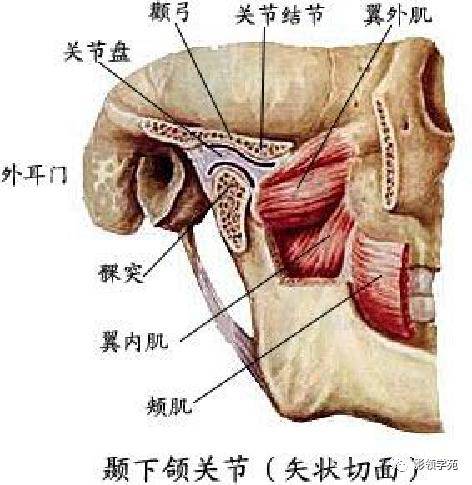

关节与韧带系统

关节与韧带系统